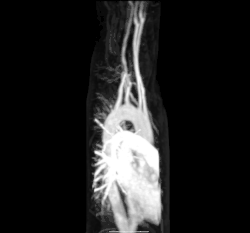

Other more invasive means can also be used. A cannula or catheter inserted into an artery may be used to measure pulse pressure or pulmonary wedge pressures. Angiography, which involves injecting a dye into an artery to visualise an arterial tree, can be used in the heart (coronary angiography) or brain. At the same time as the arteries are visualised, blockages or narrowings may be fixed through the insertion of stents, and active bleeds may be managed by the insertion of coils. An MRI may be used to image arteries, called an MRI angiogram. For evaluation of the blood supply to the lungs a CT pulmonary angiogram may be used. Vascular ultrasonography may be used to investigate vascular diseases affecting the venous system and the arterial system including the diagnosis of stenosis, thrombosis or venous insufficiency. An intravascular ultrasound using a catheter is also an option.